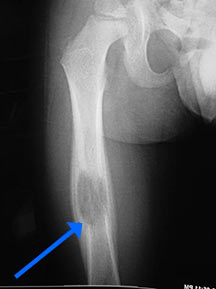

• • The work-up often consists of a physical examination, X-rays, CT scans, MRI, and sometimes bone scans are required.

Radiographic imaging is used to help form a diagnosis. These include X-Ray, MRI, CT and Bone Scans

An example of an Eosinophilic Granuloma MRI is shown.

The empty bone cavity is usually filled with bone graft or bone cement. Bone can be donated (allograft) or taken from the patient themselves (autograft). Fixation devices, such as a plate and screws, may be used in specific situations to prevent postoperative fracture.